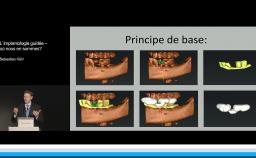

Cette conférence décrit la mise en œuvre d’un flux numérique dans le but de contribuer au respect des principes biologiques qui régissent le succès implant-prothétique. Le positionnement tridimensionnel du ou des implants est l’élément clé d’une bonne intégration tissulaire et esthétique. La possibilité d’anticiper ce positionnement lors d’une planification numérique par rapport aux tissus osseux, aux tissus mous et au projet prothétique est une plus-value importante. Autre avantage, la mise en charge et la temporisation immédiate sont plus ergonomiques. La technique est déclinée pour les édentements unitaires, pluraux, et complets.

- de comprendre les critères de positionnement implantaire

- de comprendre les principales étapes d’un flux digital pour le traitement implantaire chirurgical